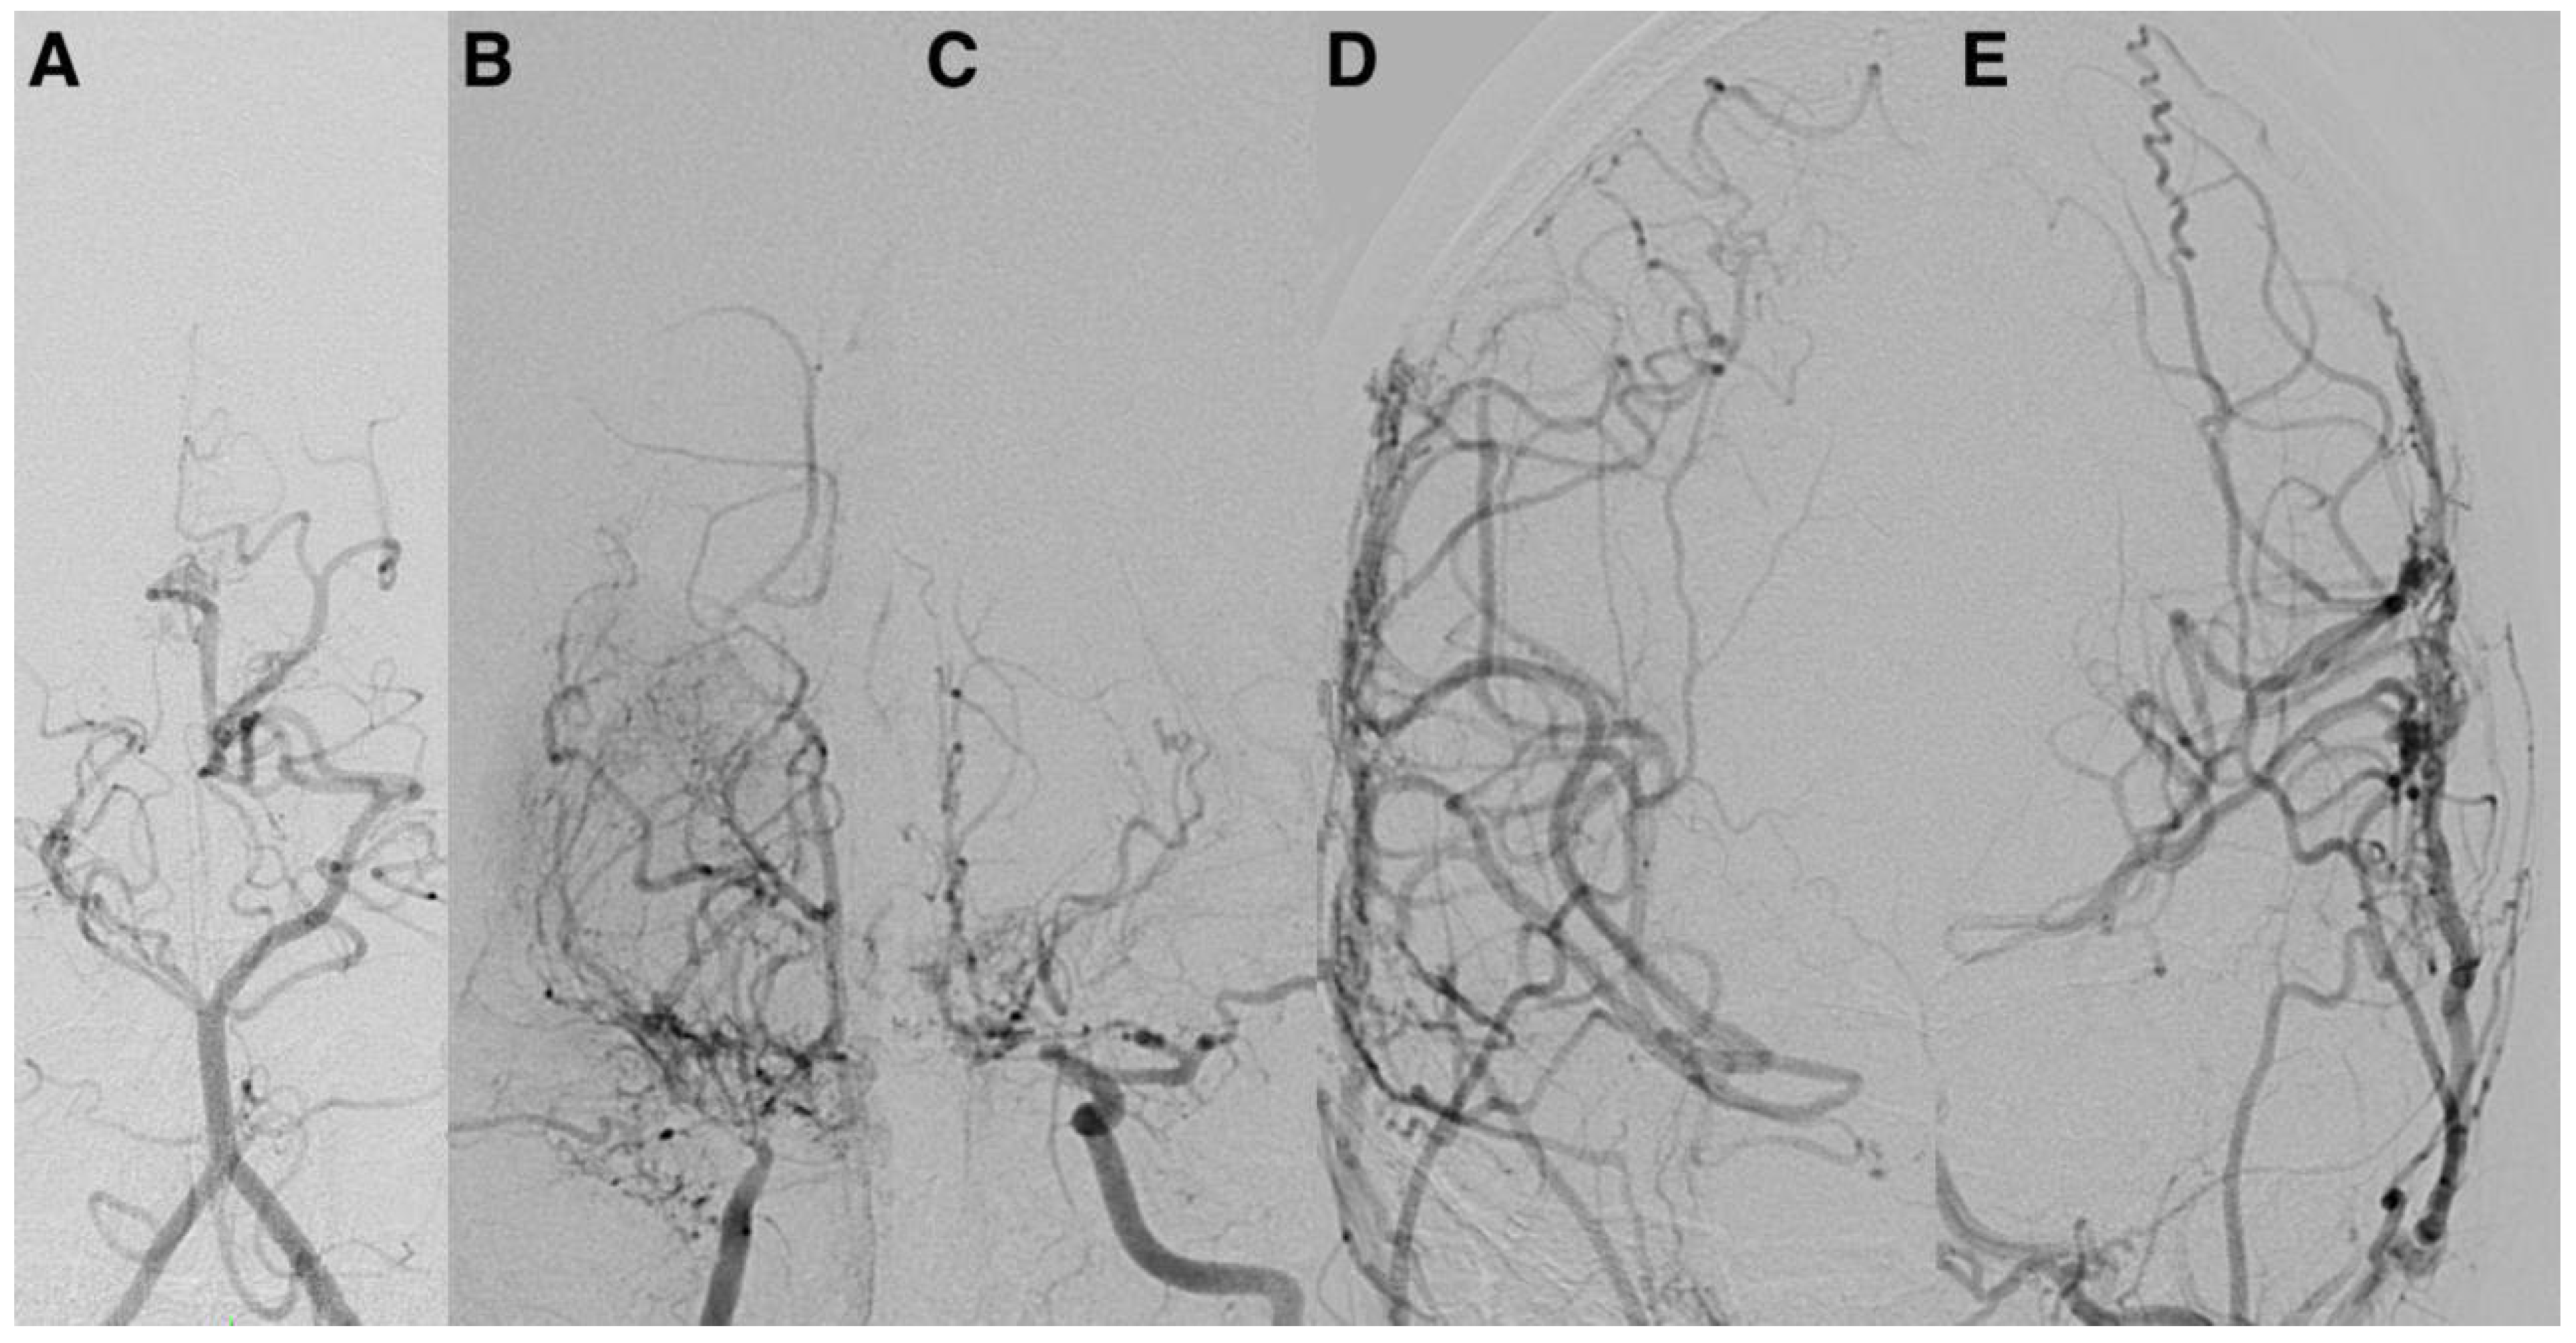

Representative postoperative angiographic images are shown in

Figure 1,

Figure 2 and

Figure 3. The mean operative time was 3.2 h and the average length of hospital stay was 7 days. All patients were monitored in the pediatric intensive care unit for 24–48 h before being transferred to the ward.

Postoperative angiographic follow-up was available for all revascularized hemispheres (n = 14). Examinations were typically performed at 3–6 months after surgery and repeated at 12–18 months in selected cases with persistent or recurrent symptoms. According to the Matsushima grading system, six hemispheres (43%) achieved grade A and 8 (57%) grade B collateralization, with no cases classified as grade C. Patients who developed grade A/B collaterals demonstrated parallel improvement in functional outcomes, with a median postoperative mRS of 1 compared to 2 preoperatively. Although the sample size precluded formal correlation testing, this qualitative relationship reinforces the functional impact of successful indirect revascularization on cerebral perfusion and recovery.